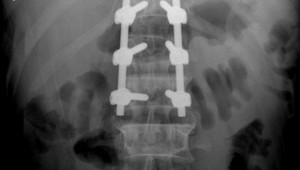

Người đàn ông 51 tuổi (ở Tuyên Quang) phải phẫu thuật cố định đốt sống do ngã xuống từ độ cao 3m dẫn đến vỡ đốt sống thắt lưng, mất vững, thoái hóa đa tầng các đĩa đệm và đốt sống thắt lưng.